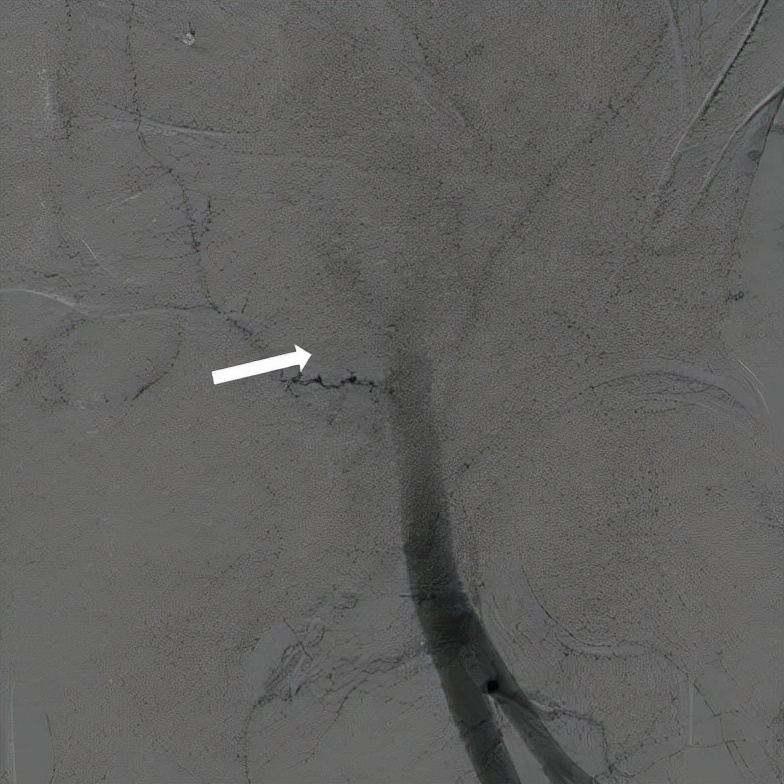

术后第三天发现患者腹胀明显,腰痛,血色素进行性下降,CT明确腹膜后巨大血肿。此时因为腹压高,CTA无法提示具体哪里出血,只能考虑左侧髂动脉可能性大。遂紧急介入,找到出血小分支后球囊堵塞30分钟无效,植入带膜支架。腹膜后血肿是经股动脉介入治疗的并发症之一,在经股动脉TAVR中尽量使用普通J头导丝,避免使用泥鳅导丝,全程透视跟进,可以很好的避免此并发症。

本例患者就是考虑泥鳅导丝刺穿分支小血管导致腹膜后血肿。腹膜后血肿CT很好诊断,但是很难明确出血血管,只能是介入下靠手术医生的经验去寻找犯罪血管,封堵的方法有球囊封堵,明胶海绵,弹簧圈,和带膜支架,可以根据犯罪血管的大小灵活选择。

CT提示左侧腹膜后、髂窝及腹股沟区巨大血肿

行急诊手术 腹主动脉及左侧股动脉造影

左侧股动脉见造影剂外渗

球囊压迫后植入覆膜支架